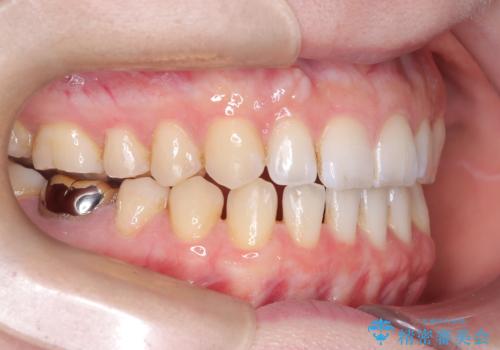

すきっ歯・切端咬合・空隙歯列|インビザラインで11ヵ月で治療完了

- すきっ歯と切端咬合(上下の前歯が先端で当たるかみ合わせ)を主訴にご来院された患者様です。

矯正検査を行った結果、非抜歯でインビザラインによる治療が可能と判断し、マウスピース矯正で改善を行いました。

11ヵ月で矯正治療が終了し、前歯の隙間も改善、見た目とかみ合わせも良好な状態となり、患者様にも大変ご満足いただけました。